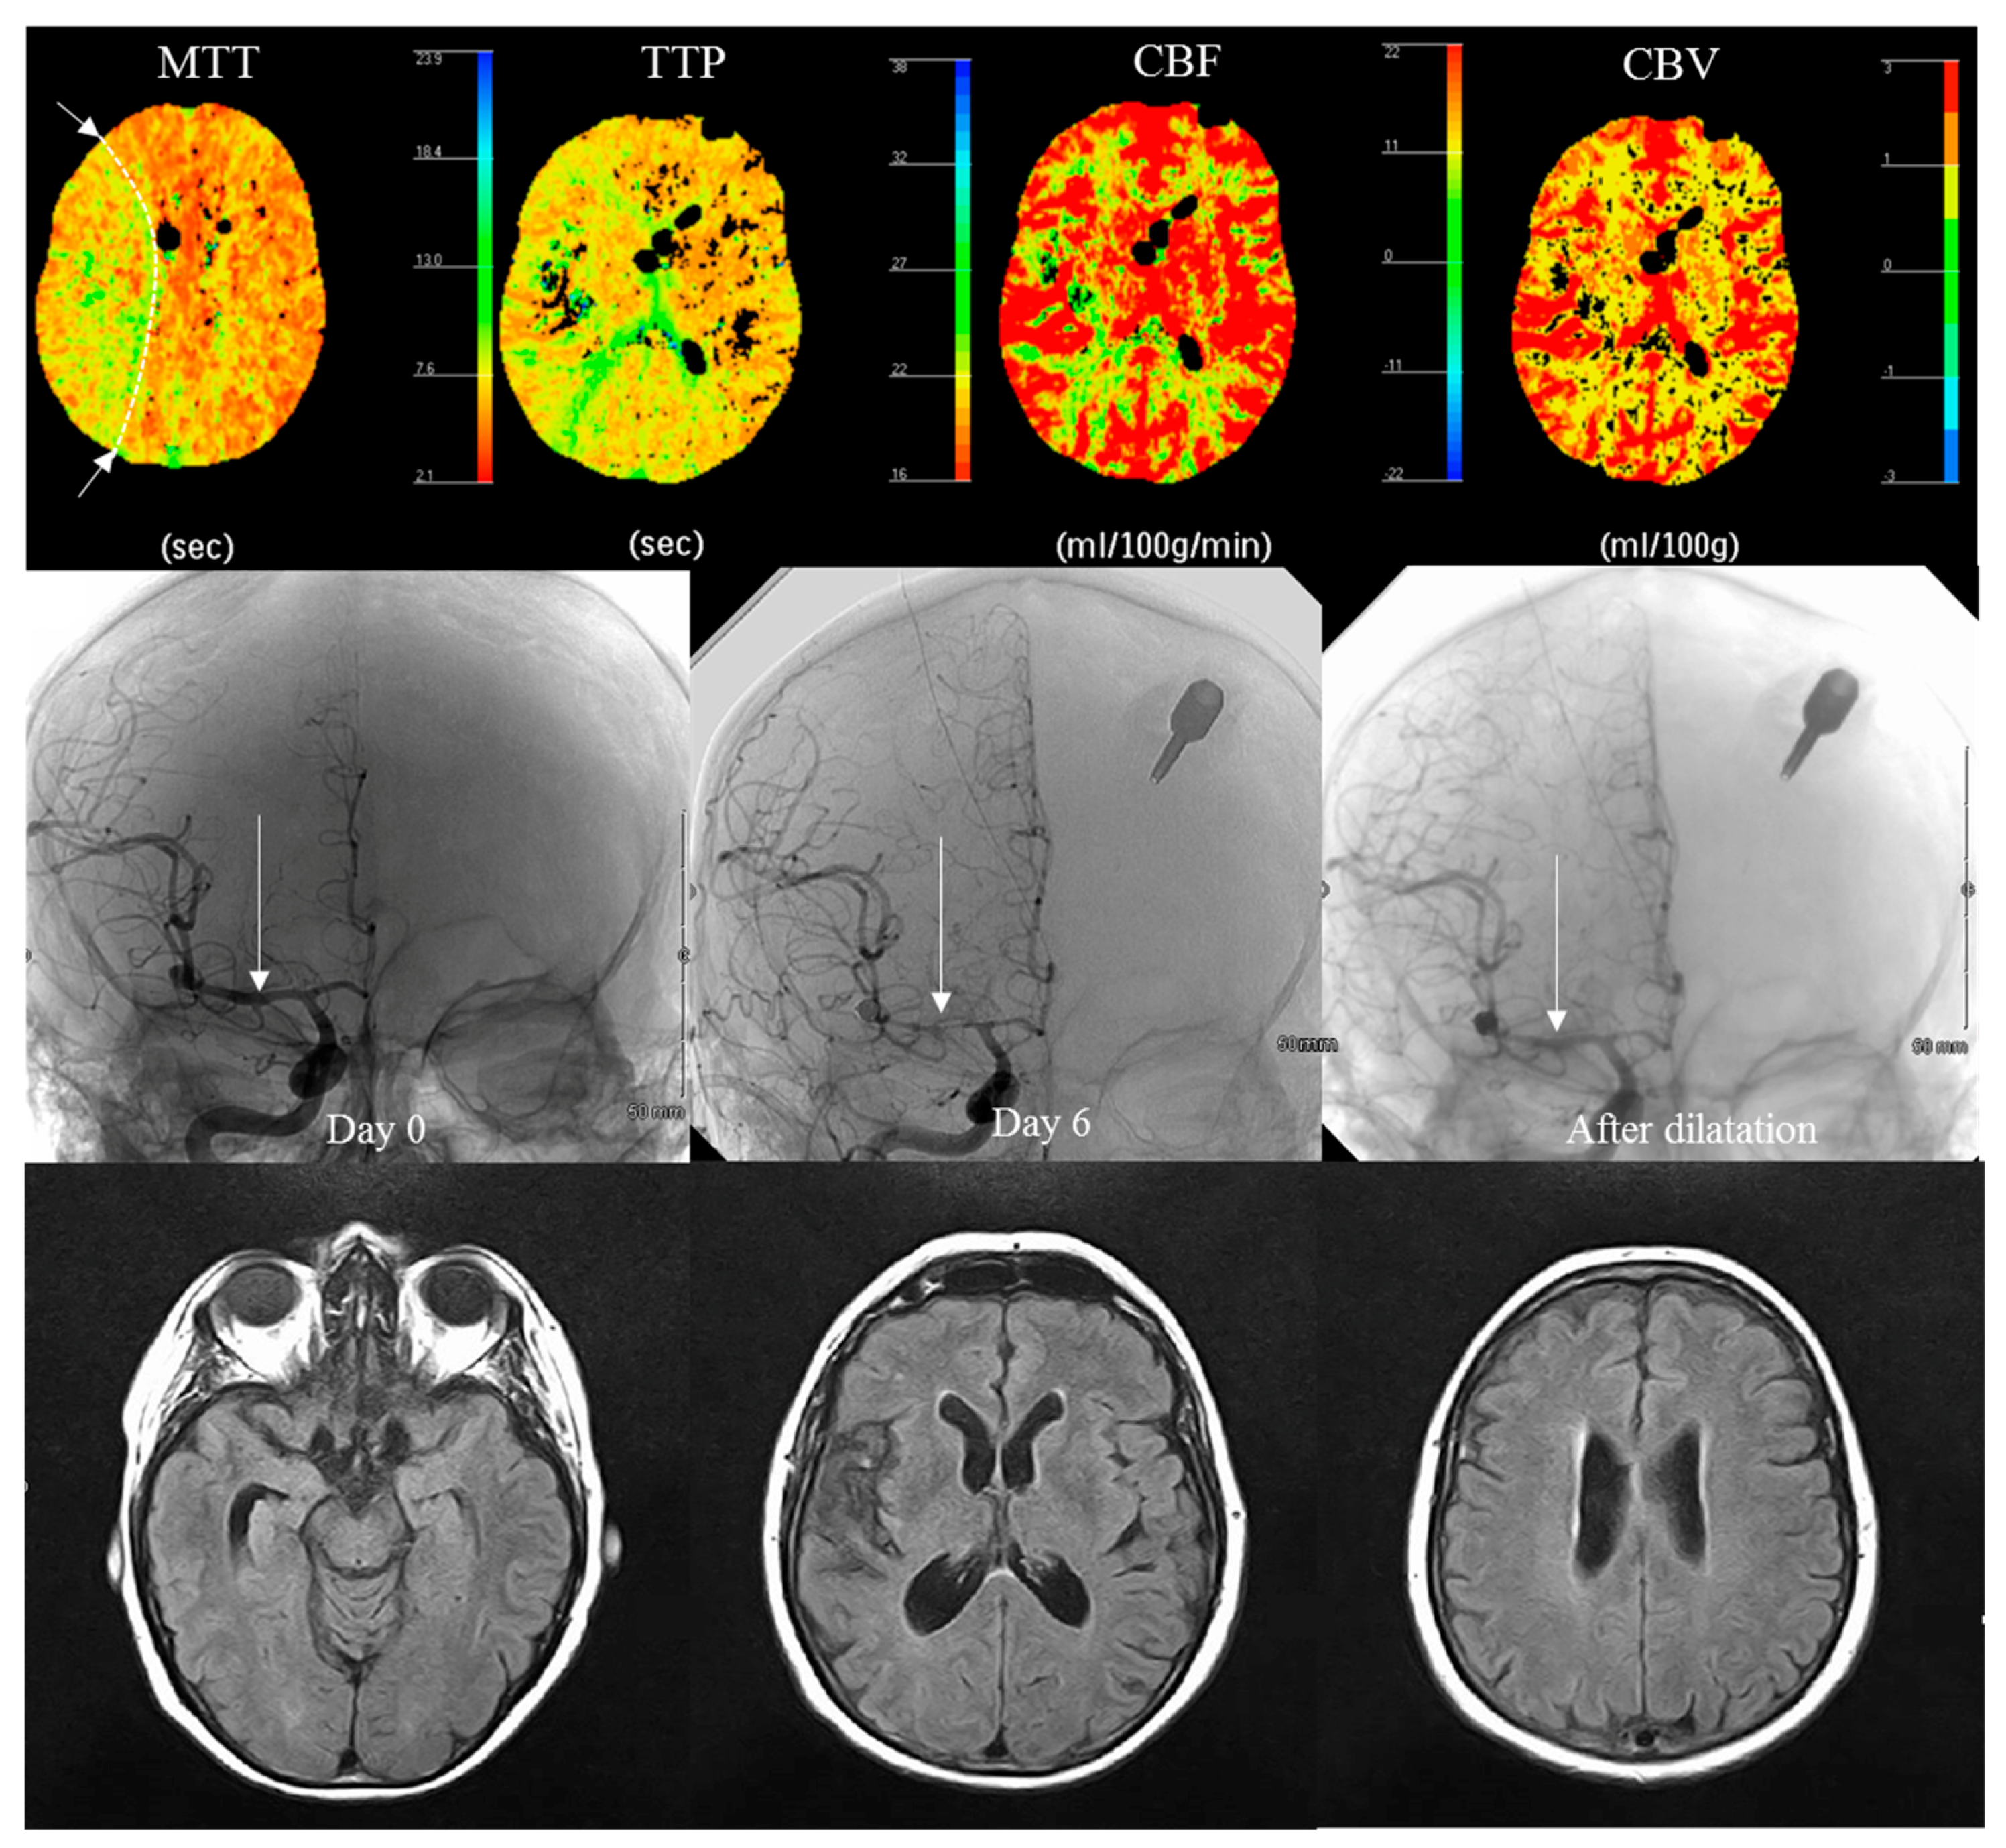

| Perfusion scanner (PCT) | ||||

| Perfusion abnormality | 12 (40) | 5 (17) | 0.084 & | |

| Anterior cerebral | 1 | 0 | ||

| Sylvian | 9 | 5 | ||

| Junctional | 2 | 0 | ||

| Angiography (CTA) | ||||

| Vasospasm: yes | 14 (47) | 10 (33) | 0.43 & | |

| Arterial diameter reduction Mild: 0 to 25% | 1 | 2 | ||

| Moderate: 26 to 50% | 6 | 7 | ||

| Severe: 51 to 100% | 7 | 1 | ||

| Distal/proximal | 2/12 | 4/6 | ||

| Uni/bilateral | 8/6 | 8/2 | ||

| Symptomatic | 7 (50%) | 2 (20%) | ||

| ATT (s) | 8.9 ± 14.6 (2–70) (n = 28) | 5.9 ± 7.8 (2–45) (n = 28) | 0.72 £ | |

| ATT ratio: pathological/healthy | 1.39 ± 1.41 (0.25–8.0) (n = 28) | 1.23 ± 0.68 (0.10–3.0) (n = 27) | 0.40 £ | |

| Blood volume CBV (mL/100 g) | 4.0 ± 6.2 (1–35) (n = 28) | 5.5 ± 7.7 (1–30) (n = 28) | 0.33 £ | |

| Blood flow (mL/100 g/min) | 38.0 ± 17.5 (4.5–70) (n = 28) | 37.3 ± 12.5 (15–60) (n = 27) | 0.80 £ | |

| p < 0.0001 & | No/Mild Vasospasm (n = 39) | Moderate Vasospasm (n = 13) | Severe Vasospasm (n = 8) |

|---|---|---|---|

| Perfusion abnormality: None | 37 (94.9%) | 6 (46.2%) | 0 (0%) |

| Perfusion abnormality: Yes | 2 (5.1%) | 7 (53.8%) | 8 (100%) |